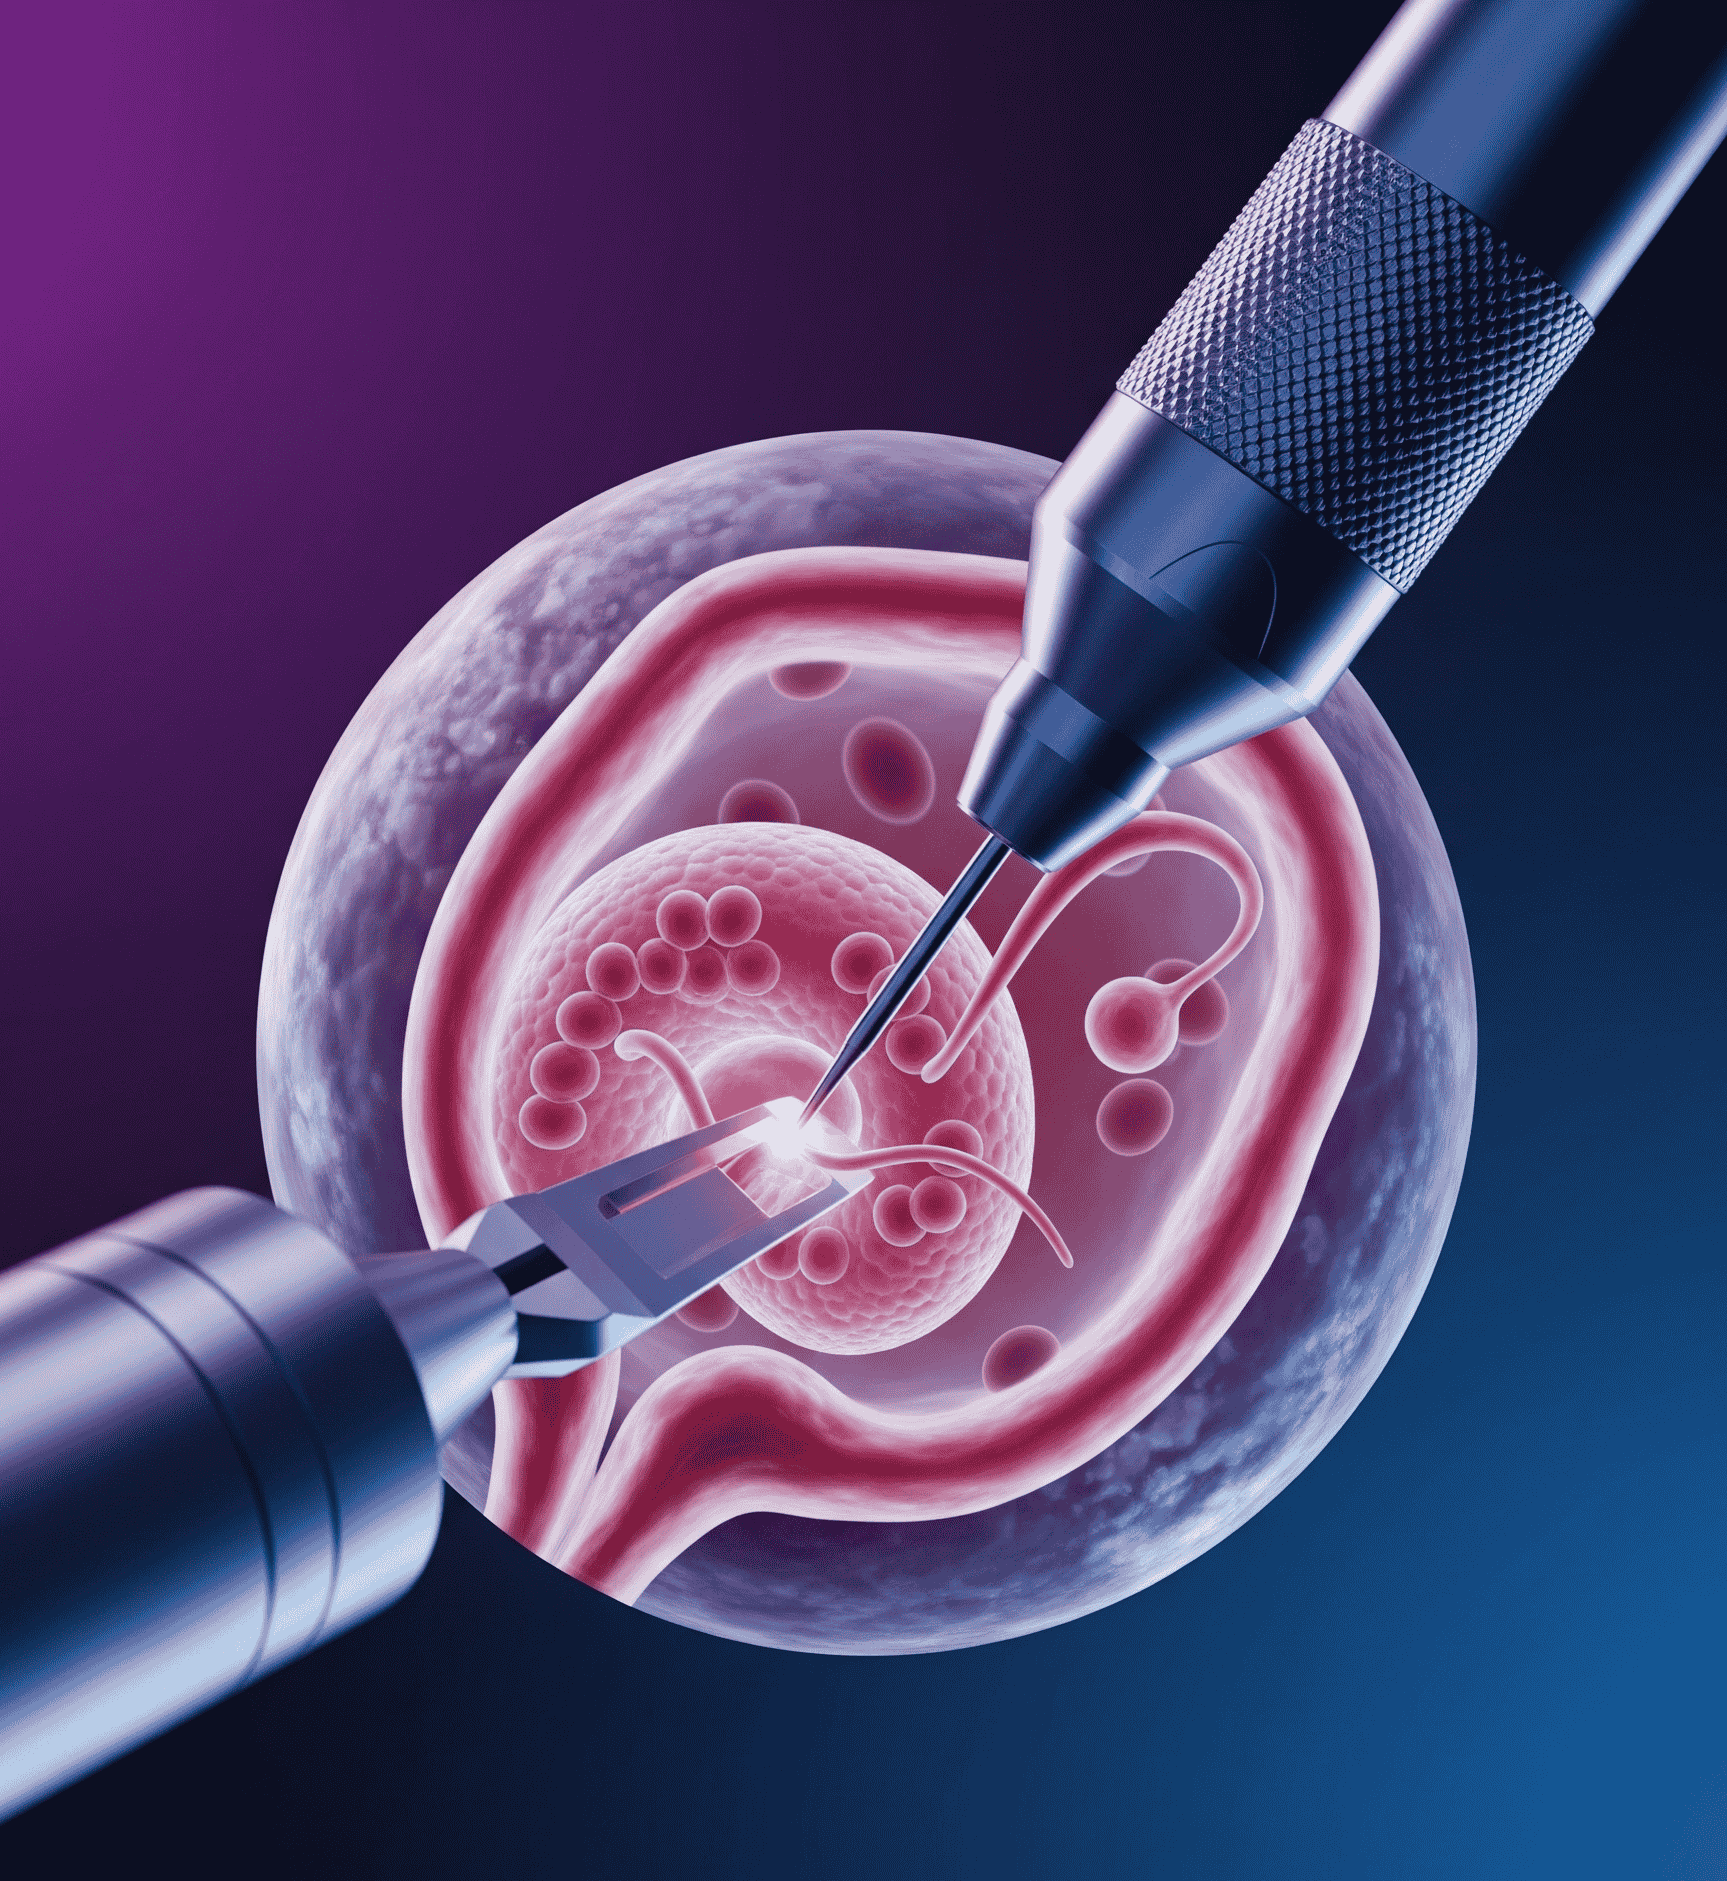

International Journal of Gynecologic Surgical Advances & Fertility Science

International Journal of Gynecologic Surgical Advances & Fertility Science is a premier peer-reviewed publication dedicated to the latest research, innovations, and clinical practices in gynecologic surgery...